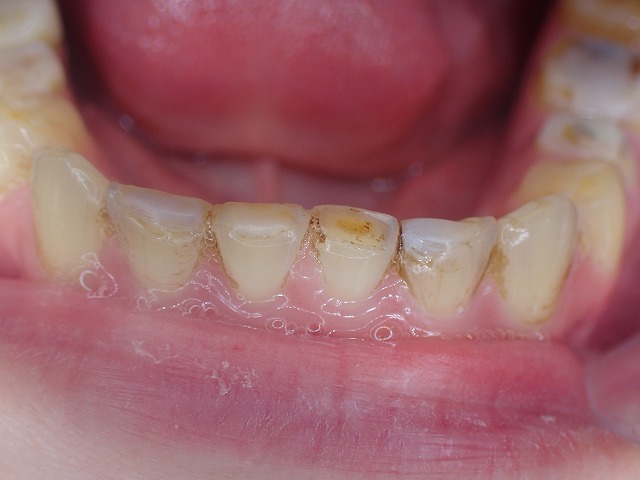

まずは下顎から診査

インビサラインのマウスピースが入っています。

下顎の前歯にレジン充填

このWEBでも再三指摘していることですが

歯ぎしりですり減った前歯の先端に

レジン充填をすると減りが加速します。

矯正のマウスピースをしているので

減りは少ないのですが、マウスピースなしでは

あっという間に吹き飛ぶリスクがあります。

下顎前歯の先端は歯ぎしりで大きく摩耗している

●歯の長さ40%が失われている

●先端がレジン充填されている–やらないほうがいい治療

●レジン充填で歯の切端を充填すると、

咬合圧力で吹き飛ぶリスクが高い

(この症例ではリテイナーが入っているので先端は割れにくい)